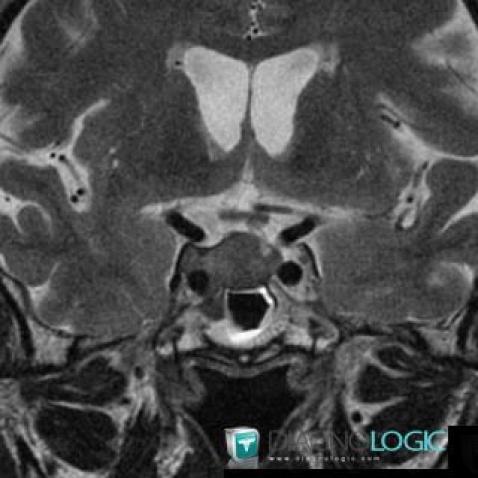

Pituitary macroadenoma, Pituitary gland and parasellar region, MRI

Here is the specific information in the key image above:

- Diagnosis Pituitary macroadenoma, Location(s) Pituitary gland and parasellar region, with gamuts Cavernous sinus lesion